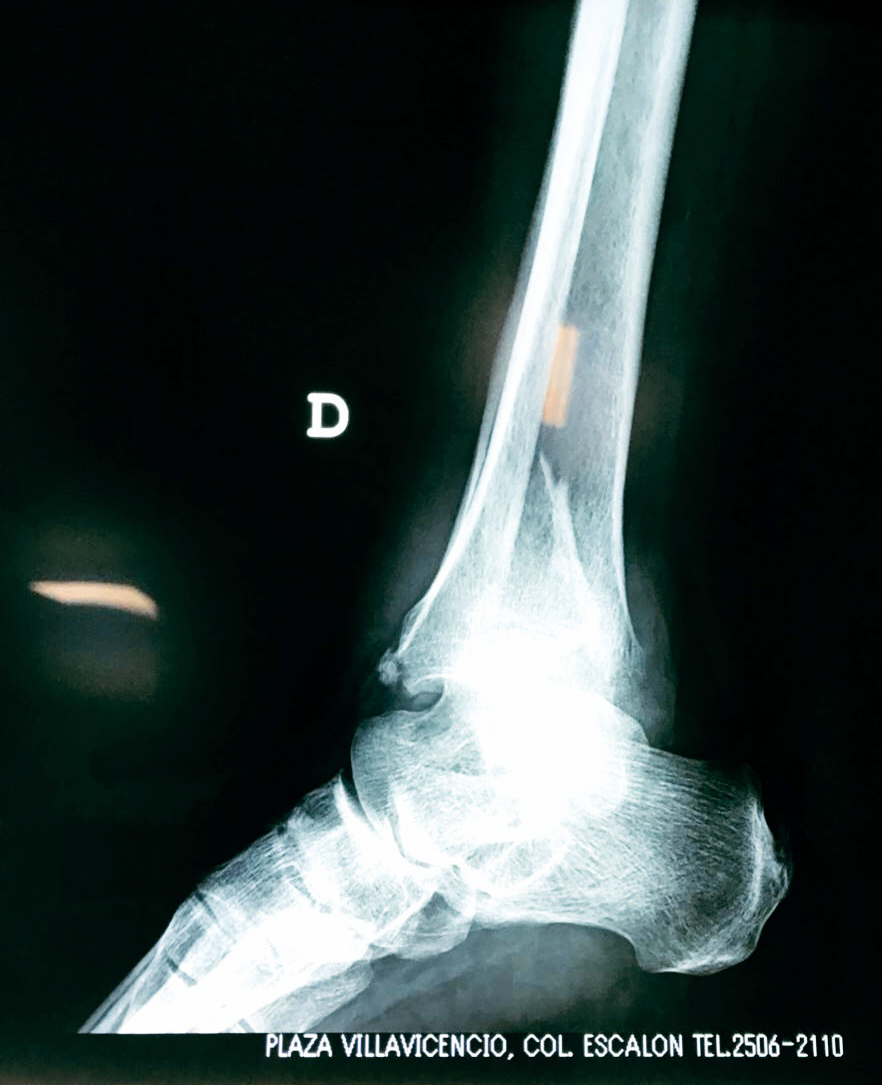

Algunas fracturas de tobillo pueden requerir cirugía si:

- Los extremos de los huesos están desalineados entre sí (desplazados).

- La fractura se extiende hasta la articulación del tobillo (fractura intra-articular).

- Los tendones o ligamentos (tejidos que sujetan los músculos y los huesos entre sí) están rotos.

- El médico cree que sus huesos probablemente no sanen apropiadamente sin cirugía.

- El médico considera que la cirugía puede permitirle una recuperación más rápida y confiable.